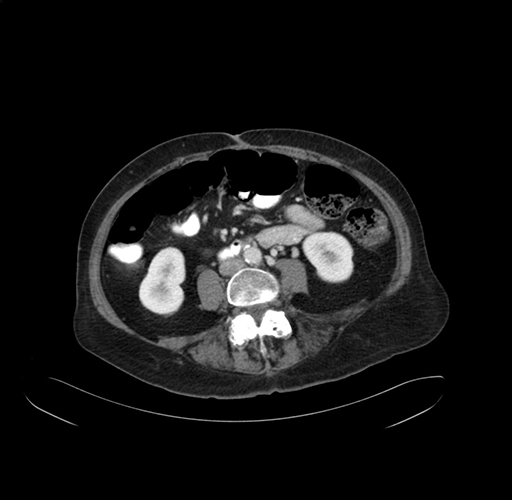

Pre-Chemo: Axial Venous

Axial Venous